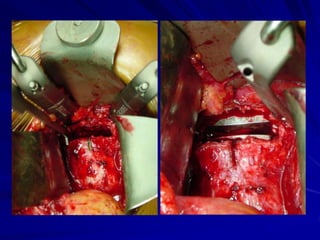

Chord compression at C4-C5 left side

Lateral view after

Prodisc-C implantation

ΑΡ view after

Prodisc-C implantatio

MRI pre-surgery.

DDD multilevels -

Chord

compression at C4-

C5

Chord compression

at C5-C6 pre-surgery

Flexion and Extension

after Prodisc-C

implantation at level C5-

C6

Prodisc – C in neutral

position and in lateral

bending